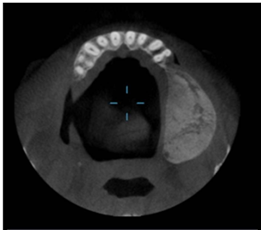

The investigations advised included the complete blood picture, intraoral periapical radiograph, maxillary occlusal view, panoramic radiograph and CBCT. Periapical radiograph and maxillary left lateral topographical occlusal view a revealed diffuse patchy radiolucency in region of 26, 27 along with multiple flecks of fine calcifications and hypercementosis was seen with respect to 28 (Figure 2) (Figure 3). Panoramic view revealed radiopacity extending from 24 to tuberosity and encroaching onto the maxillary sinus (Figure 4). To make out the exact extent of the lesion CBCT imaging was planned. CBCT sections showed mixed radiopaque radiolucent (predominately radiopaque) lesion, with well defined borders, extending from 24 till tuberosity region (Figure 5) measuring anteroposteriorly 4cm ,superoinferiorly 5cm ,and mesiodistally around 2.5cm in dimension. The pterygoid plates though intact, the lesion however did superimpose on the maxillary sinus. No secondary reaction in the sinus could be appreciated. With a clearer picture on the extent of the lesion, we took the next step towards the management.

Figure 5 CBCT sections showed mixed radiopaque radiolucent (predominately radiopaque) lesion, with well defined borders.

6. A unilocular radiolucency interposed between divergent or resorbed roots. Waldron CA and Giansanti16 stated that all OF invariably show a thin radiolucent line surrounding the lesion representing capsule and sometimes a sclerotic rim present within the host bone at the margin that may be smooth and delicate or it may be slightly irregular, more diffuse and of varying thickness. In our present case the CBCT showed a mixed radiolucent radiopaque lesion of size 4cmx5cmx2.5cm encroaching the maxillary sinus surrounded by a radiolucent line causing expansion and thinning of the cortical plates, mimicking the Eversole type 4 OF.